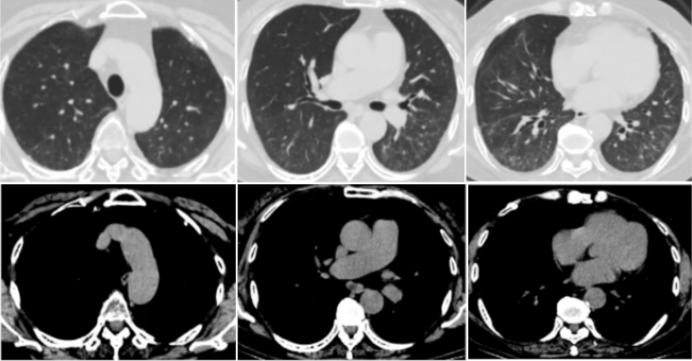

11月27日胸部CT:双肺间质性炎症局部较前(11月10日)略吸收,双侧胸腔积液(图9)

图片

9  复查胸部CT(2023-11-27)

2024年2月22日随访胸部CT示: 双肺间质性炎症全部吸收(图10)。继续予甲泼尼龙片40 mg qd、尼达尼布150 mg bid治疗, 经风湿免疫科会诊, 予环磷酰胺1.0 g每月1次冲击治疗。

10  随访胸部CT(2024-02-22)